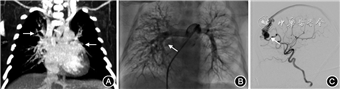

诊疗经过:患儿入院后因发绀明显予空氧混合仪鼻导管吸氧,C反应蛋白最高116 mg/L,痰培养提示铜绿假单胞菌,痰宏基因检出肺炎链球菌、无乳链球菌等多种细菌,脑脊液检查及血培养无异常,予抗感染治疗,静脉输入丙种球蛋白支持治疗。血、尿串联质谱、甲状腺功能、新生儿遗传代谢筛查未见异常。入院8 d患儿仍有呼吸费力、气促表现,转监护病房,予经鼻高流量吸氧,SpO2仍不能维持在0.90以上,遂予气管插管机械通气,SpO2回升。超声心动图示卵圆孔未闭,胸部CT平扫无明显异常,增强CT提示两肺内小血管偏多,血管畸形待排除,纵隔多发小血管,两肺多发条索影及渗出(图1A),考虑肺动静脉畸形(pulmonary arteriovenous malformation, PAVM)。为明确有无其他内脏血管畸形,完善全身增强磁共振成像(magnetic resonance imaging, MRI)提示脑干前方、右侧额叶表面见一迂曲扩张的静脉显影,考虑为动静脉畸形。入院20 d行数字减影血管造影(digital subtraction angiography, DSA),见右肺动脉呈弥漫性葡萄串样小血管池表现,右上、右下肺静脉显影提前(图1B)。导管分别于右上、右下、左上、左下、肺静脉抽取血液,测血氧饱和度(氧分压)分别为0.863(54.9 mmHg, 1 mmHg=0.133 kPa)、0.812(51.6 mmHg)、0.880(59.2 mmHg)、0.995(117 mmHg),左房血氧饱和度(氧分压)0.927(66.7 mmHg),提示右肺和左上PAVM。同时术中脑血管造影证实大脑前动脉供血的软脑膜动静脉瘘(图1C)。PAVM诊断明确。患儿家属放弃治疗出院。入院27 d基因回报提示KAT6B及SERPING1基因位点变异,为与患儿表型部分相关的临床意义未明位点。